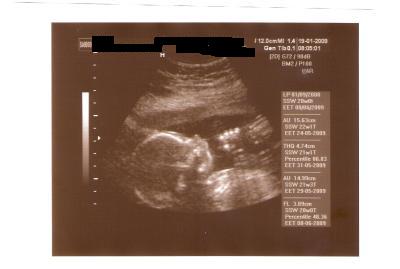

Gestern hatte Würmchen wieder Untersuchungstermin und wurde wahrlich auf Herz und Nieren (und Arme, Beine, Magen) geprüft. Alles da und alles dran.

Wir befinden uns jetzt in der 20.SSW. Halbzeit!